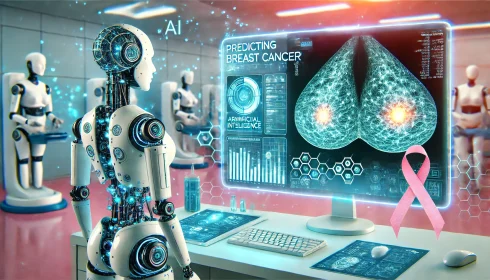

هوش مصنوعی عملکردی برتر در پیشبینی سرطان سینه دارد

در یک مطالعه جامع منتشر شده در مجله Radiology، الگوریتمهای هوش مصنوعی عملکرد برتری نسبت[بیشتر بخوانید]